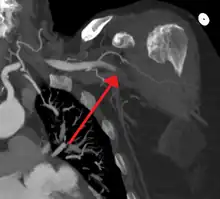

| Acute embolism to the right femoral artery resulting in ischemia | |